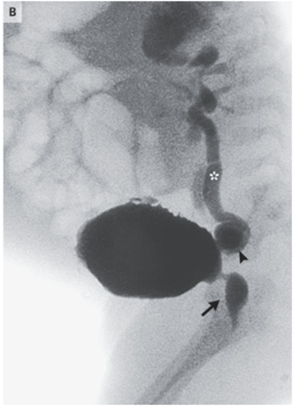

妊娠中に診断される子宮頸がんは、母体の根治的治療と胎児の生命維持という、極めて複雑な倫理的・医学的判断を要する疾患です。本ソースでは、妊娠10週でFIGO 20…